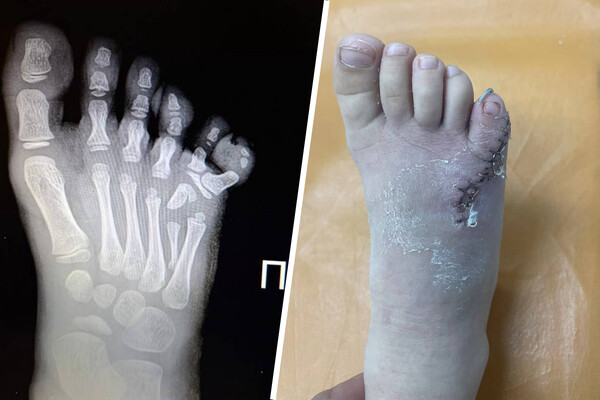

Врачи прооперировали четырехлетнюю россиянку с шестью пальцами

В Липецкой области врачи удалили четырехлетней девочке шестой палец на ноге

Врачи Ельцкой детской больницы прооперировали ребенка с полидактилией — врожденной особенностью, когда у человека есть лишние пальцы на ногах или руках. Об этом сообщили в пресс-службе администрации Липецкой области.

Медики отметили, что из-за своей особенности четырехлетняя пациентка жаловалась на боль в ступне. Также ребенку было сложно подобрать подходящую обувь.

Операцию девочке провел травматолог-ортопед Махач Алиев.